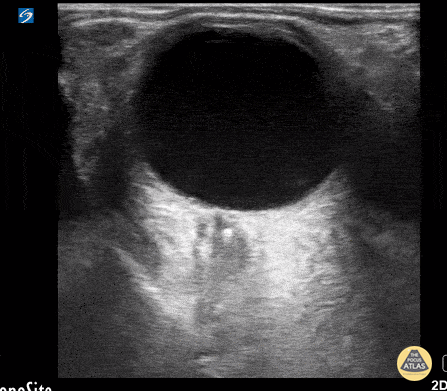

Orbital - Central Retinal Artery Occlusion

This is from a 63 year old female who initially presented to the emergency department with vision loss over the last 24 hours. She reported bending over when she experienced complete vision loss from one of her eyes. Point of care ultrasound was performed, locating the optic nerve, but more interestingly a hyperechoic structure within the nerve (spot sign). Overall, this is was suggestive of a central retinal artery occlusion. In this sort of situation, color doppler can also be utilized to assess for arterial versus venous occlusion. Dr. Christopher Paulo, DO, PGY-1 Riverside Regional Medical Center Emergency Medicine Program (Newport News, VA)